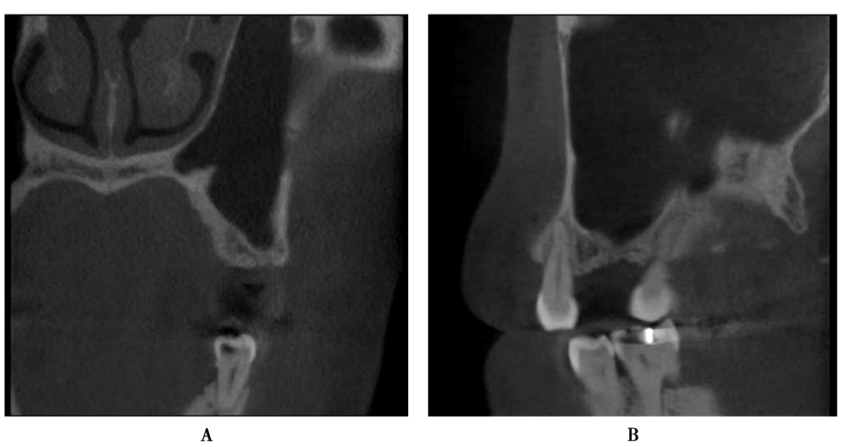

术前CBCT显示缺牙区牙槽嵴顶到上颌窦底的最小高度约3mm,上颌窦底黏膜约1mm,上颌窦腔影像清澈,无炎症,侧壁厚度1~2mm(图12)。

图12 术前CBCTA.冠状面;B.矢状面

术后CBCT,见上颌窦内有血液充盈,但骨粉充填良好,未见骨粉弥散,保持了良好的形态(图14),提示胶原膜对穿孔起到了良好的封闭。

图14 术后CBCT,可见窦腔有积液A.矢状面;B.冠状面

完成修复6个月后复查,CBCT三维方向显示种植体周围有充分的骨组织支持。上颌窦内的血液彻底吸收,窦内黏膜无增厚,窦腔放射影像重新变为透射,说明上颌窦有一定的自愈能力(图16)。

图16 修复6个月后复查CBCTA.冠状位;B.矢状位;C.水平位